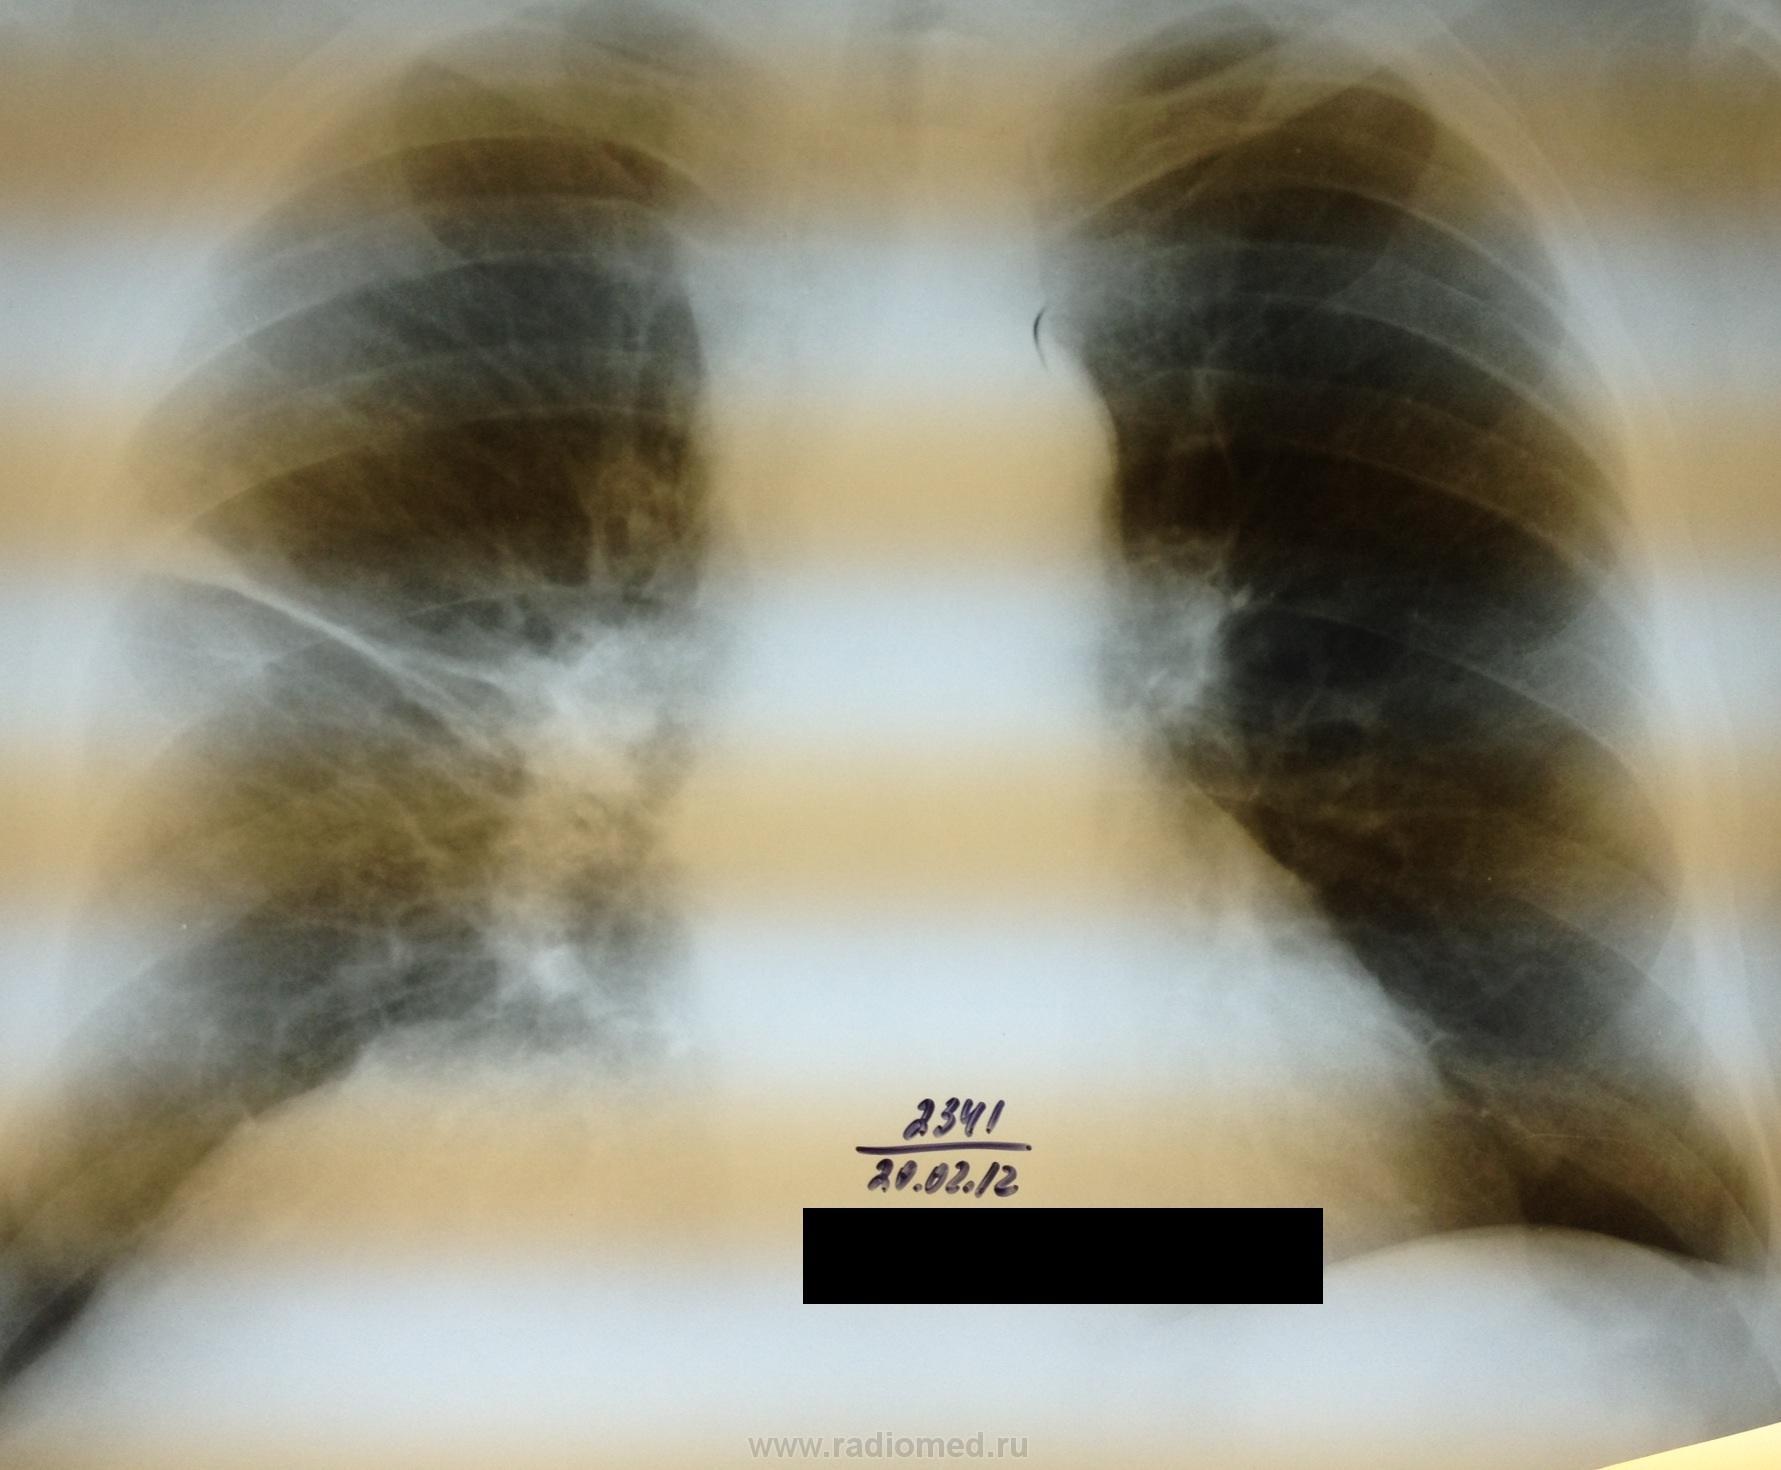

Скорее всего реакция плевры. Я считаю, что динамика есть, при чем положительная.(?)

Согласен, это не сильно выражено, но тяж как будто стал аккуратнее, легочной рисунок чище.

Где этот тяж на боку? Или это не в легком, а на плевре? Возможно по ходу малой м/д плевры в передних отделах?